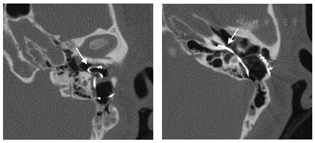

耳内镜:左外耳道内可见脓性分泌物,内镜下清理后见人工耳蜗电极导线自外耳道后壁突入外耳道内,呈不规则盘曲。左侧鼓膜表面少量分泌物,鼓膜紧张部及松弛部未见穿孔。右侧鼓膜完整,标志清楚(图1)。

耳内镜下左外耳道内可见脓性分泌物,清理后见人工耳蜗电极导线自外耳道后壁突入外耳道内,鼓膜未见穿孔。右侧鼓膜完整,标志清楚。纯音测听检查:双侧极重度感音神经性聋。颞骨高分辨率CT检查示左外耳道内可见高密度电极导线影,耳蜗内电极已大部分脱出于蜗外,仅电极尖端部分留存于耳蜗底周。左侧中耳乳突炎。右侧外耳道及鼓室腔干净。